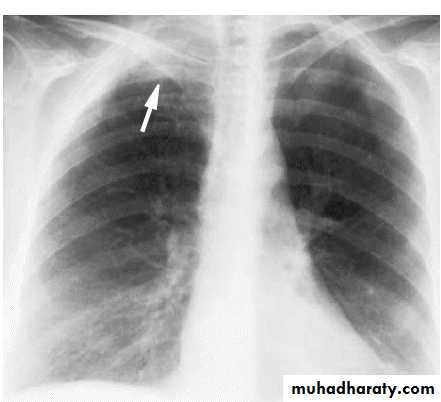

Pleural effusionX-ray of pleural effusion

Massive right effusion